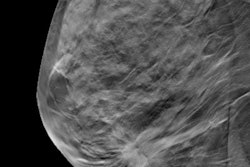

Could digital breast tomosynthesis (DBT) be a standalone option for breast cancer screening? New research adds heft to the evidence supporting its viability.

In a large study, DBT detected more than twice as many cancers as full-field digital mammography alone. It also yielded better performance than a combination of the two technologies.